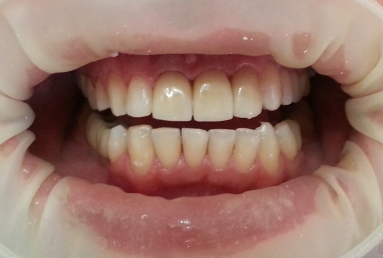

The orthodontic treatment was necessary as the upper maxillary developed assimetricaly, also the teeth were malpositioned. The purpose of the partial braces was to help the final prosthetic treatment, which consisted of two full ceramic crowns for the central incisors, that had root canal treatments, and a ceramic veneer for the lateral incisor, that had a large composite filling. Gingivectomies were also necessary for the right canine and incisors in order to correct the assymetrical gummy smile.